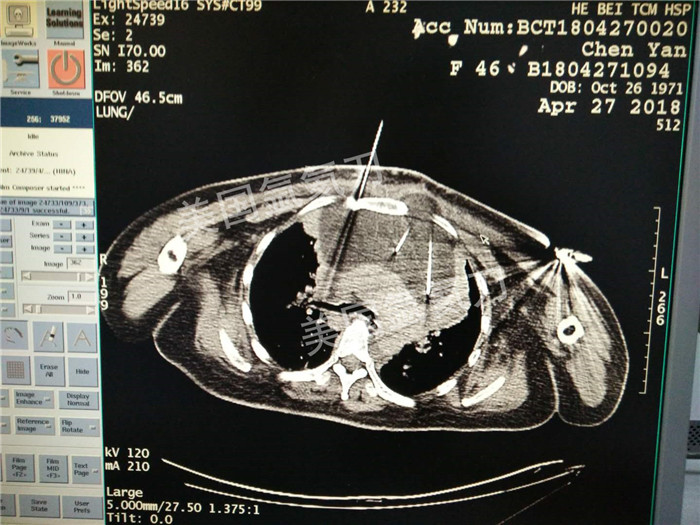

河北省中医院肿瘤科王利民主任胸腺19公分肿瘤氩氦刀手术

图片版权归美国氩氦刀所有,仅用于美国氩氦刀的宣传交流